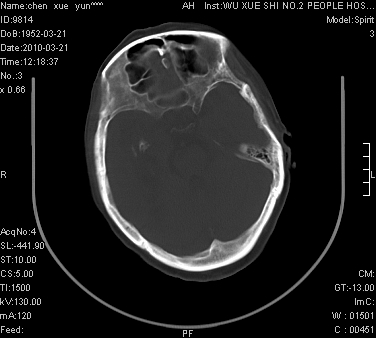

性别:不详;年龄:58岁;病史:不详。

ct表现:1、右侧额颞叶深部不规则钙化密度团块,呈弯曲条带状,占位效应不明显,考虑少枝胶质细胞瘤可能性大于血管瘤。2、右枕叶大片不规则低密度影,密度近似于脑脊液,右侧侧脑室后角及三角区扩张,考虑为陈旧性脑梗塞。

讨论:1、这个病灶的钙化有点像脑回样钙化,因此我最初考虑颅面血管瘤病(sturge-weber综合征),但是查阅了我们网站上的几个颅面血管瘤病病例,钙化均位于脑实质表面,沿脑回分布,而这例病灶位置较深,因此可以否定“颅面血管瘤病”这个诊断。

2、卜一会员曾经说过:少枝胶质细胞瘤的典型征象为弯曲条带状钙化,可作为定性的可靠征象(http://www.radida.com/news_view.asp?id=5150)

3、血管瘤也可以出现弯曲条带状钙化,但血管瘤多数出现“负占位”效应,即病灶周围的脑室、脑池及脑沟不是受压变窄,而是局限性的增宽。